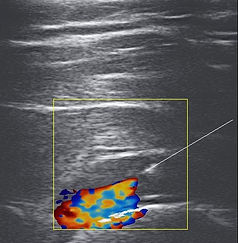

어깨초음파주사

초음파 유도하 어깨주사

1. 인대강화주사 (초음파시술)